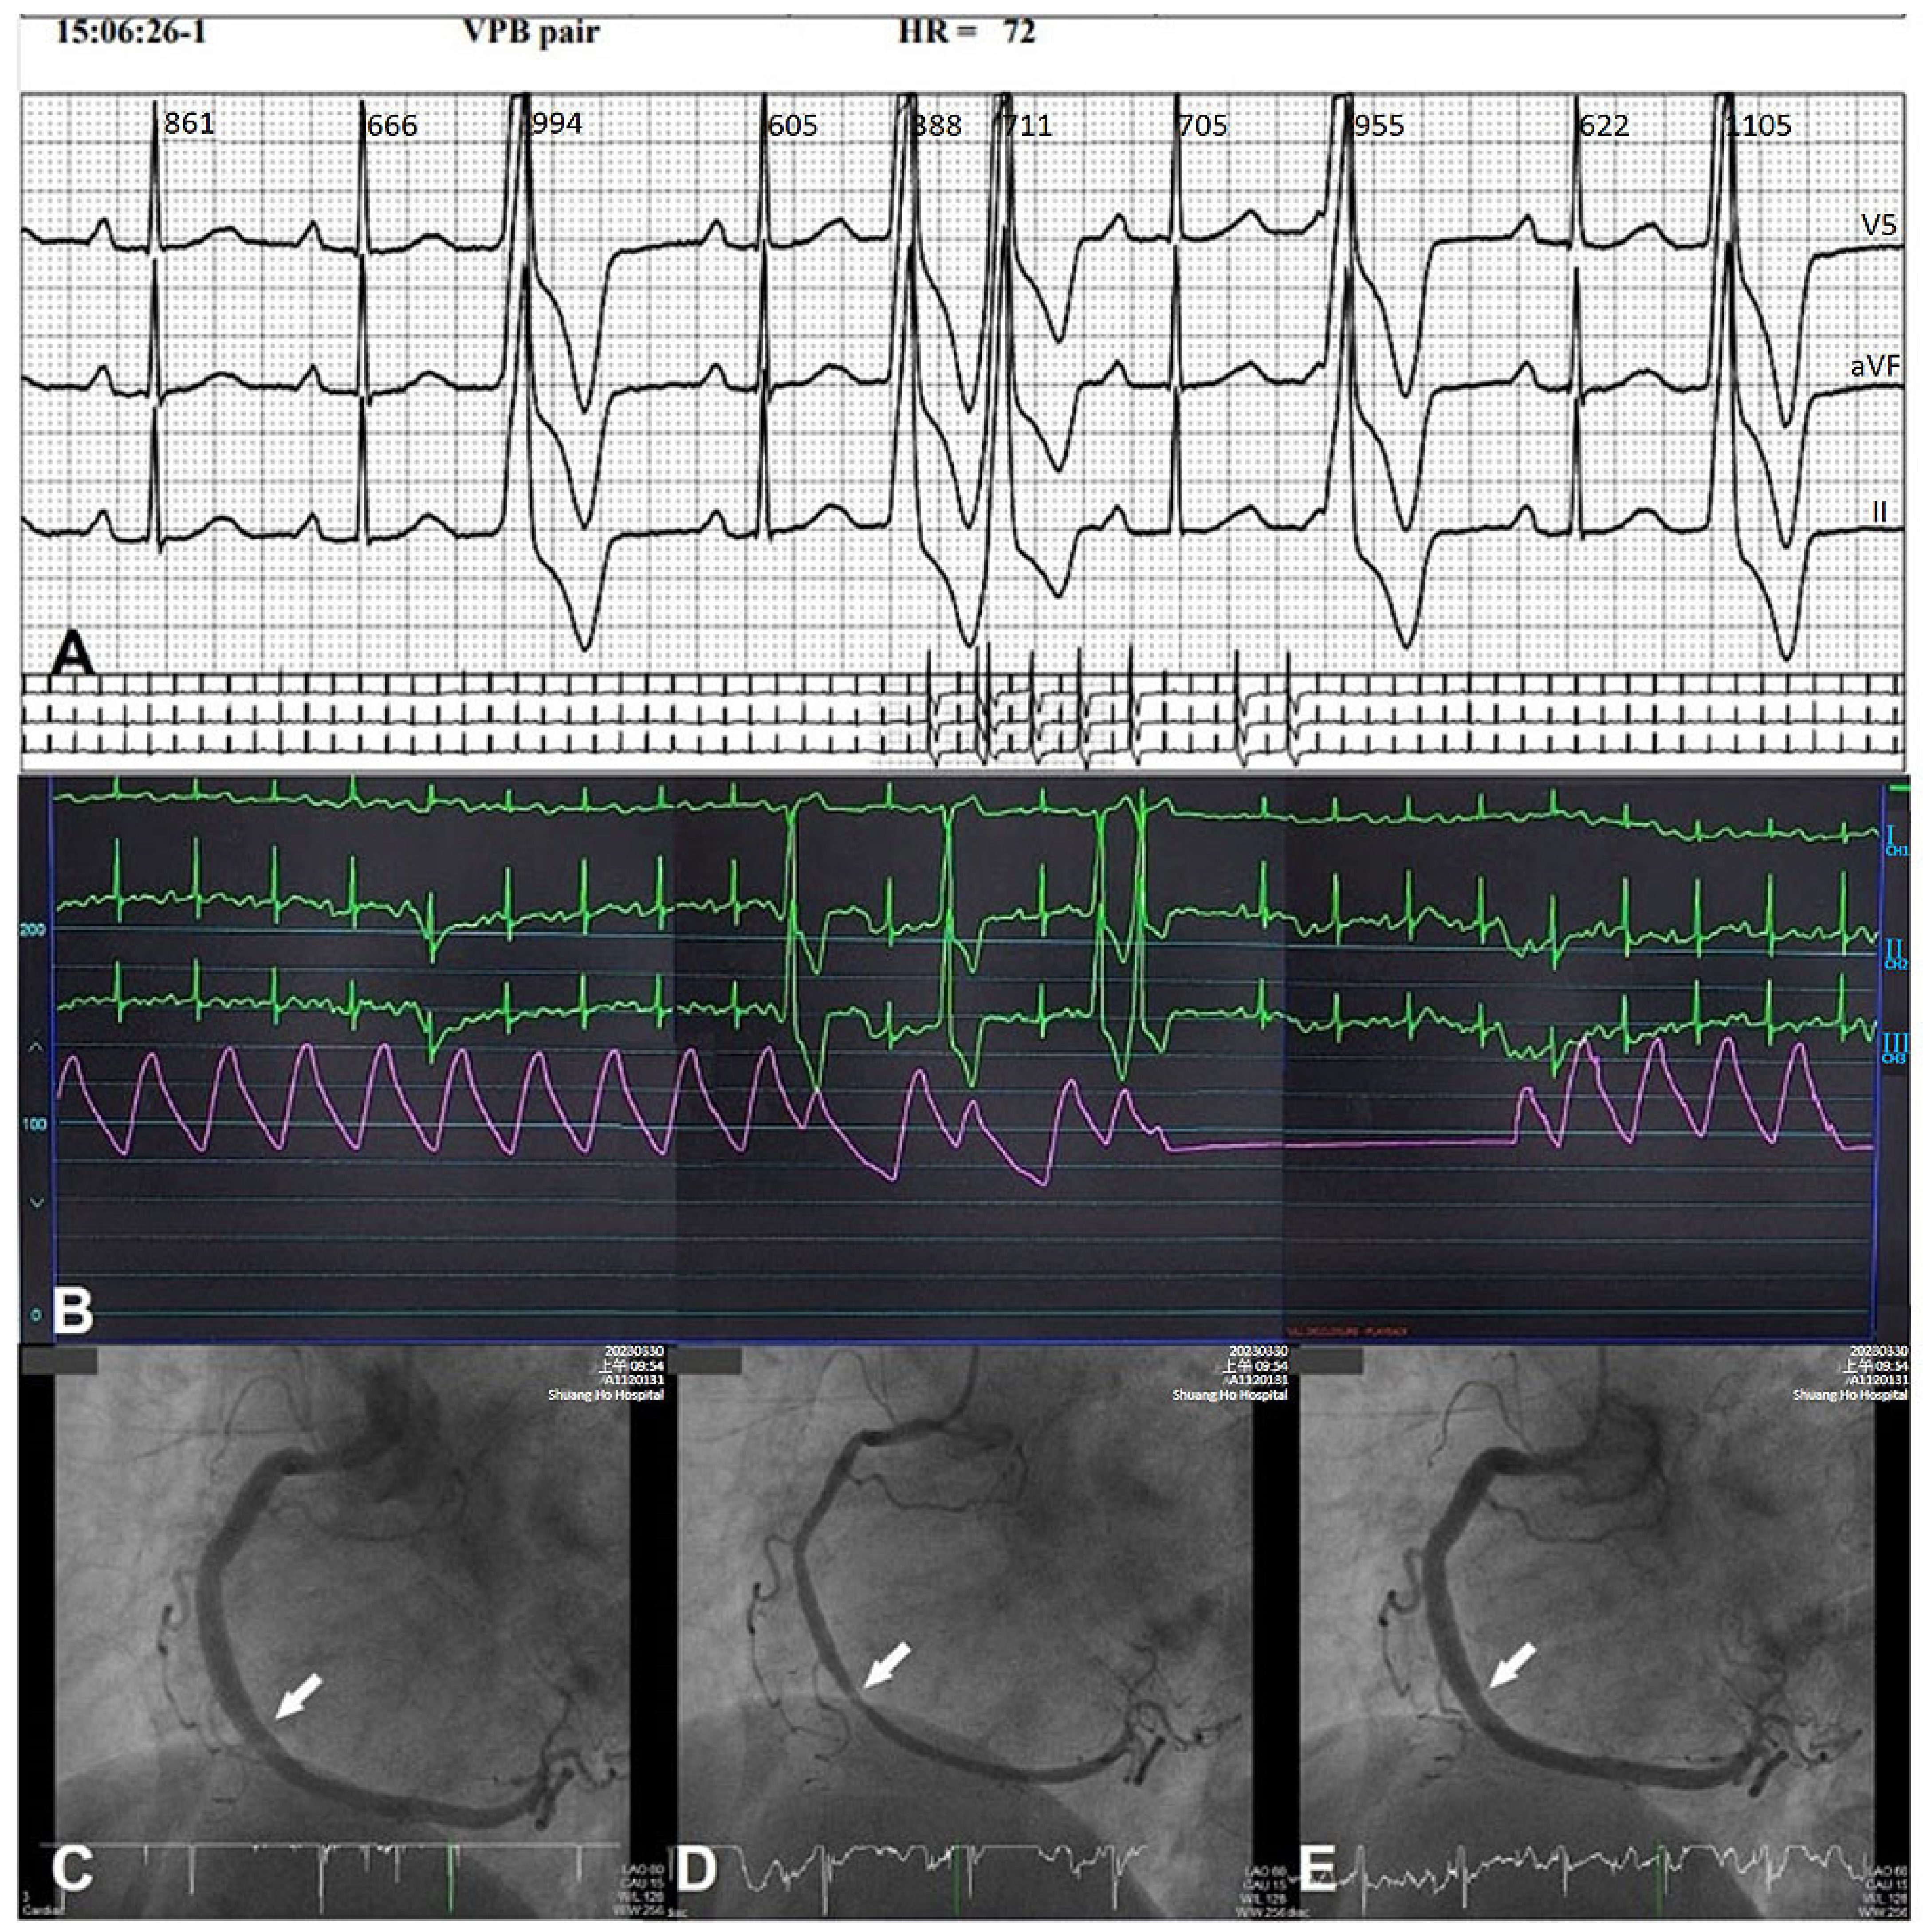

- Hung, M.J.; Cheng, C.W.; Yang, N.I.; Hung, M.Y.; Cherng, W.J. Coronary vasospasm-induced acute coronary syndrome complicated by life-threatening cardiac arrhythmias in patients without hemodynamically significant coronary artery disease. Int. J. Cardiol. 2007, 117, 37–44. [Google Scholar] [CrossRef] [PubMed]